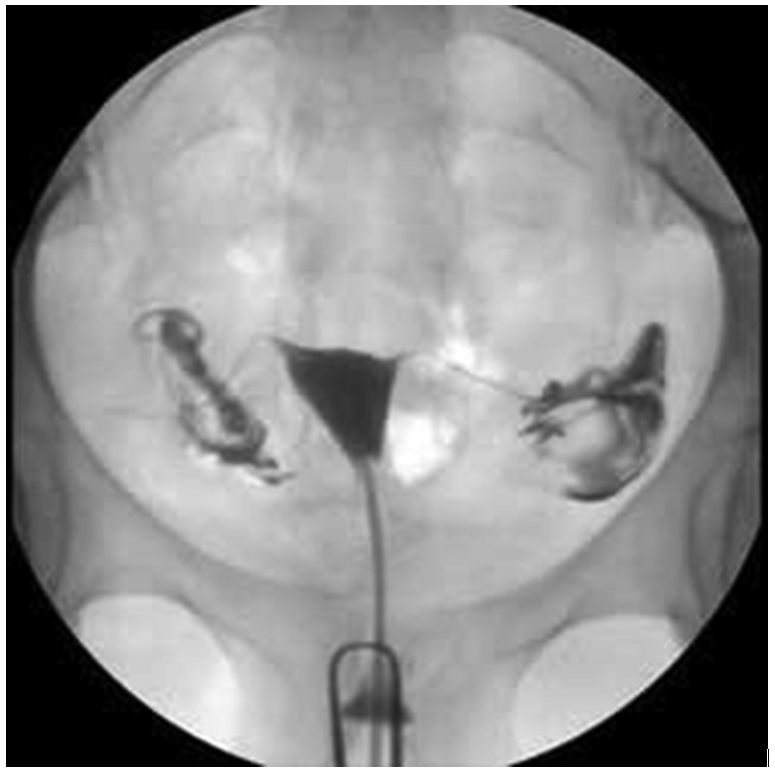

A hysterosalpingogram, HSG is an X-ray examination of the womb and Fallopian tubes. It aims to find out if there are any blockages in the tubes or other reasons why pregnancy might not be happening easily (polyps / fibroids).

A liquid dye (iodine contrast) which is visible on an X-ray is gently pushed into the womb.

Several external pictures are taken to follow the flow of dye inside the womb cavity to outline it and along the tubes and as it spills out of the ends.

A thin tube is then inserted into the cervix (neck of the womb) and a colourless X-ray dye is injected to show the uterus and tubes A period type pain may be felt at this point, but should soon settle as the dye begins to leak out.